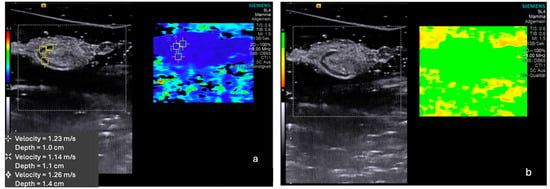

2.2. Shear Wave Elastography (SWE)